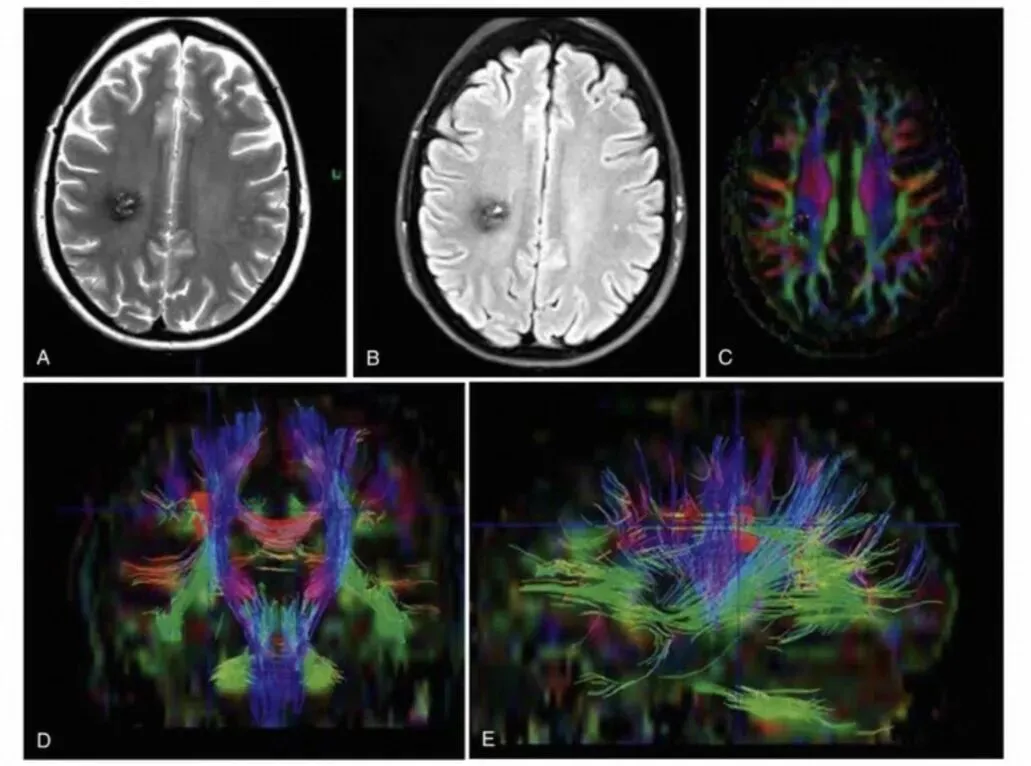

这部巨著共四卷,总计超过4500页,内容全面,涵盖了神经外科的各个方面,包括功能与恢复性神经外科、神经肿瘤学、脑血管疾病、脊柱与周围神经手术等。第8版在上一版的基础上进行了全面更新,反映了该领域的最新进展,新增了55个章节,内容涉及扩散张量成像、机器人手术、人工智能在神经外科的应用等前沿话题。